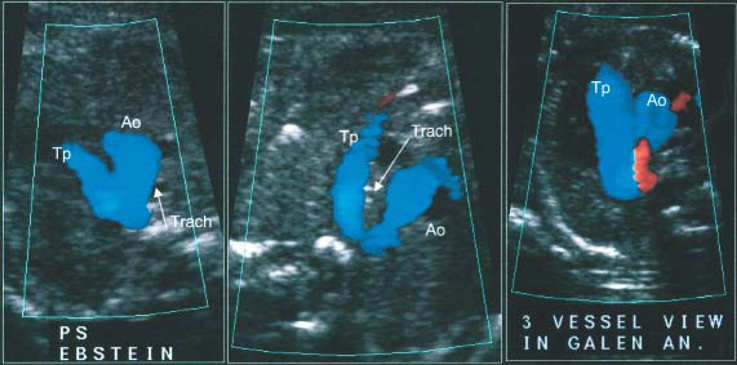

胎児心臓診断においてもTei indexは,これまで多くの論文で胎児の心機能評価として引用されている.Ebstein奇形,動脈管閉鎖など,心機能が変化するような心臓病では異常値を示す11, 12).Inamuraらは2005年にEbstein奇形を含めた三尖弁異形成疾患群において,LV Tei indexと生命予後とが関係すると報告している11).2013年にGhawiらは,それまでの13年間で報告された胎児Tei indexの正常値をまとめた上で,胎児自験例の計測から正常値は,左室Tei index 0.464+/−0.08,右室Tei index 0.466+/−0.09と報告しており,成人における左室0.38+/−0.05,右室0.28+/−0.04に比し高値となっている13).

I-shaped signは,TGAにおいてthree vessels and trachea viewを描出した際に,大動脈が前方にある右室から起始して長く後方に向かい動脈管弓と合流するまでが「I」の字のように描出されることを見いだし,TGAの胎児診断に有用であると2013年にIshiiらが報告した指標である19)(Fig. 2).具体的には31例のTGA症例で後方視的に確認したところ,I-shaped signを30例に認めたとしている.その後2015年にはPalatnikらが,I-shaped signの有用性を検討し,TGAの胎児24例のうち23例(95.8%)でI-shaped sign陽性であったことからもこの指標がTGAの胎児診断において簡便かつ迅速に診断するのに有用と述べている27).今後もその有用性が期待される指標である.